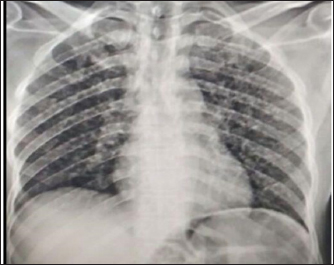

Upon investigation, chest X-ray showed multiple bilateral air space nodules (Fig. 2); abdominopelvic U/S showed numerous hypoechoic splenic lesions; complete blood count was non-remarkable; urine lipoarabinomannan (LAM) was positive, and Xpert MTB/RIF assay from the left axillary skin abscess was positive for rifampicin sensitive Mycobacterium tuberculosis (Table 1).

Fig. 2. Chest X-ray revealed multiple bilateral air space nodules.